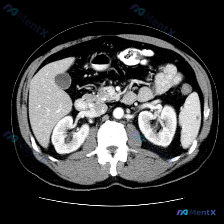

整理了一份很有意思的影像读片案例,一开始容易被提问带偏,仔细看下来其实是一个非常好的“临床思维”训练。 --- 病例基本情况 用户提出的问题是:“图像中描绘的具体异常是什么?脾脏病变”,附带了一幅腹部CT横断面(软组织窗)图像。 关键影像表现 我梳理了一下图像里的核心信息: 1. 脾脏:大小、形态正...

最近看到一个很有意思的影像分析场景,整理了一下思路和大家分享。 先看基础情况 用户预设了“脾脏病变”的方向,提供了一张腹部CT横断面软组织窗图像,从分析来看是增强扫描的动脉期或早期门脉期。 这张CT的核心表现 先整理一下明确的阳性/阴性信息: ✅ 图像质量:清晰度良好,无明显运动/金属伪影,软组织辨...

整理了一份很有意思的读片病例,差点被最初的提问带偏,分享一下思路: 病例背景 核心提问是“这张图里脾脏有什么病变?”,先来看影像的客观描述。 关键影像信息(增强CT横断面) 1. 扫描层面与质量:上腹部增强,对比度好,结构清。 2. 我们重点看的脾脏:边缘轮廓大致正常,未见明确局灶性低密度、高强化或...

今天看到一个挺有意思的影像分析场景:拿到一张上腹部CT横断面(软组织窗),问题直接指向“脾脏病变”,但仔细看完影像描述,我觉得这里可能藏着一个临床思维的小陷阱。先把资料理一理: --- 影像描述核心信息整理 肝脏:轮廓清晰,形态正常,肝实质密度均匀,未见明确局灶性占位,肝内血管走行自然。 脾脏:左上...

今天看到一份很有意思的腹部CT读片案例,整理一下思路和大家分享。 病例背景 用户最初的问题是「识别图中的脾脏病变」,但拿到图像(腹部CT横断面软组织窗)后,先按流程做了系统评估。 --- 影像关键信息整理 先把看到的客观情况列出来: 1. 脾脏:形态大小正常,包膜光滑,密度均匀,未见任何局灶性异常,...

最近看到一个读片资料,预设问题是“图像中是否存在脾脏病变”,先和大家理一下完整的思路。 --- 先列一下拿到的「影像客观事实」 这是一幅上腹部CT软组织窗横断面图像: 1. 肝脏:轮廓平整,实质密度均匀,肝内血管走行清晰,无受压移位; 2. 脾脏:划重点——形态正常、大小正常、实质密度均匀,未见局灶...

今天看到一个提问很有意思——直接问“脾脏病变”,但把影像资料和分析理了理,发现这里有个很典型的临床认知陷阱,整理出来和大家讨论。 先把完整客观影像信息放前面(别被提问带偏): --- 一、客观影像所见(腹部CT平扫软组织窗) 1. 图像质量:伪影少,软组织对比度好,满足诊断 2. 关键解剖结构: -...